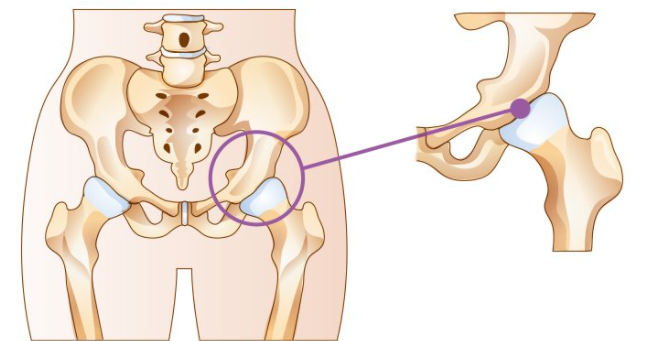

고관절은 골반과 대퇴골을 이어주는 관절입니다. 그래서 엉덩이관절, 엉덩관절 등 여러명칭으로 불리고 있습니다. 고관절이 불편하거나 통증이 있다면 하체를 움직이기에 불편함이 커집니다.